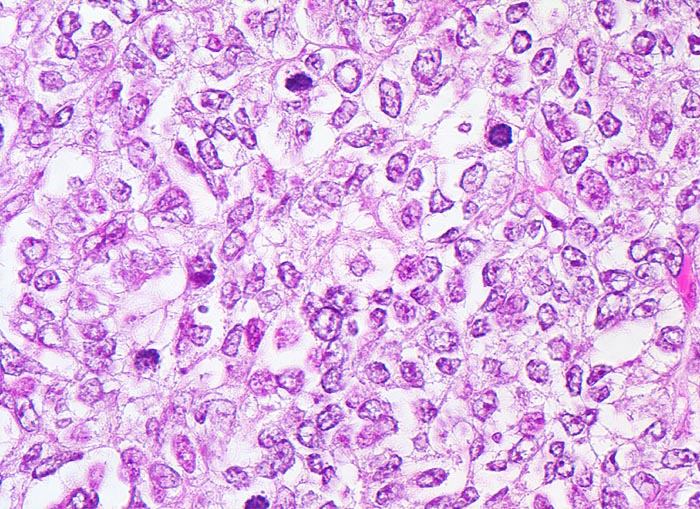

Endometrioide Karzinome bestehen aus tubulären Drüsen, welche von einem mehrreihigen Epithel ausgekleidet werden. Schleim ist meist nicht oder nur apikal in den Zellen vorhanden. Die Ausdehnung der soliden Areale und die zytologischen Atypien bestimmen den Differenzierungsgrad (low-grade versus high-grade). Metaplastisches Plattenepithel findet sich häufig in endometrioiden Karzinomen und hilft bei der Abgrenzung von anderen Subtypen. Das endometrioide Karzinom kann sich innerhalb von Adenomyoseherden im Myometrium entwickeln (> 4482). In diesen Fällen kann die Bestimmung der Infiltrationstiefe erschwert sein.

• Endomyometranes Gewebsfragment.

• Die rechte Seite des Uteruskavums wird ausgekleidet von flachem atrophem Endometrium. Im Cavum liegt ein Blutkoagel mit nekrotischem Detritus nach vorausgegangener diagnostischer Utersukurettage.

• Anstelle des Endometriums findet sich in der linken Hälfte des Uteruskavums ein Adenokarzinom bestehend aus architektonisch komplexen Drüsen. Die Drüsen liegen teils dos à dos ohne erkennbares Stroma zwischen zwei Drüsenschläuchen.

• Tumorzellverbände infiltrieren die glatte Muskulatur des Myometriums.

• Tumordrüsen ausgekleidet von mehrreihig angeordneten Tumorzellen mit hyperchromatischen polymorphen längsovalen Tumorzellkernen mit zahlreichen Mitosen. Die Morphologie der Tumordrüsen erinnert an proliferatives Endometrium.

• Anmerkung: Typischerweise ist das endometrioide Karzinom des Uterus als Folge des ursächlichen Hyperöstrogenismus assoziiert mit einem hyperplastischen Endometrium (siehe Präparat 148). Im Kurspräparat erscheint hingegen das nicht-neoplastische Endometrium nach vorausgegangener Kurettage atroph. Atrophes Endometrium findet sich sonst charakteristischerweise neben serösen Endometriumkarzinomen postmenopausaler Patientinnen. Das sollte der Kliniker dem Pathologen mitteilen: